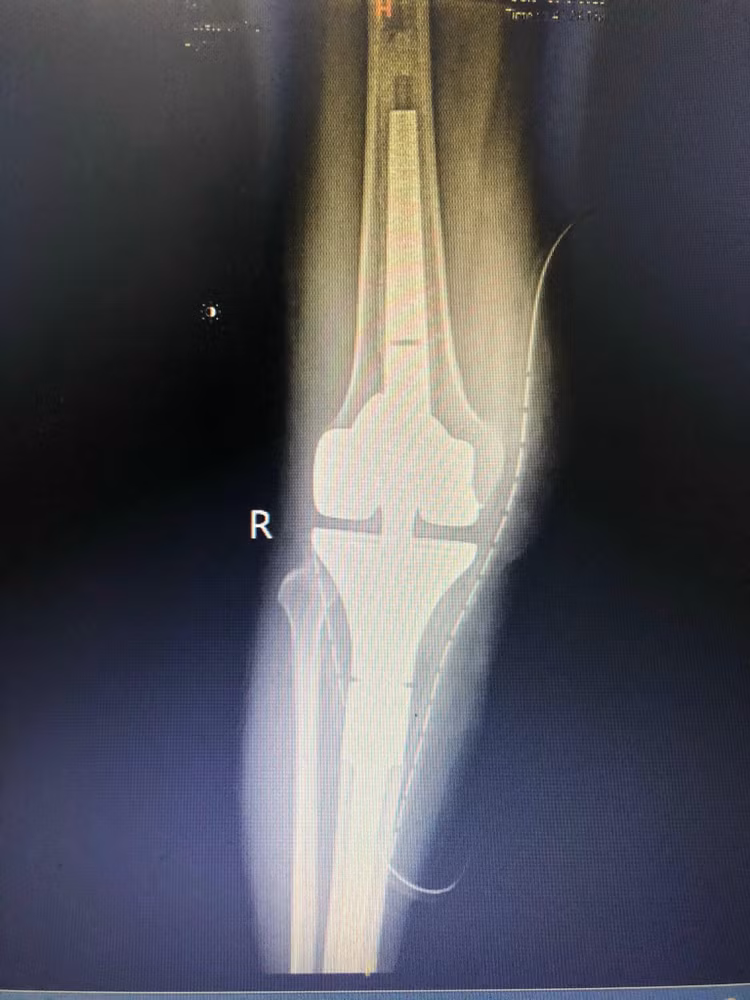

![]() |

| Bệnh nhân được thay khớp toàn phần |

Đánh giá trong phẫu thuật khối u tế bào khổng lồ xương chày phải tái phát lan rộng xâm lấn cơ 1/3 dưới đùi phải, các bó cơ cẳng chân phải bó mạch khoeo chân phải, u ôm lấy động mạch khoeo chân và thần kinh hông to, thần kinh chày và thần kinh mác sâu, xâm lấn toàn bộ diện khớp xương chày phải một phần diện xương bánh chè và lồi cầu trong xương đùi.

Bệnh nhân được cắt rộng xương chày có u và một phần đầu dưới xương đùi và các bó cơ bụng nhân cơ tứ đầu đùi thâm nhiễm, thay toàn bộ khớp gối phải dạng modul chuôi dài cá thể hóa theo tổn thương u của bệnh nhân.